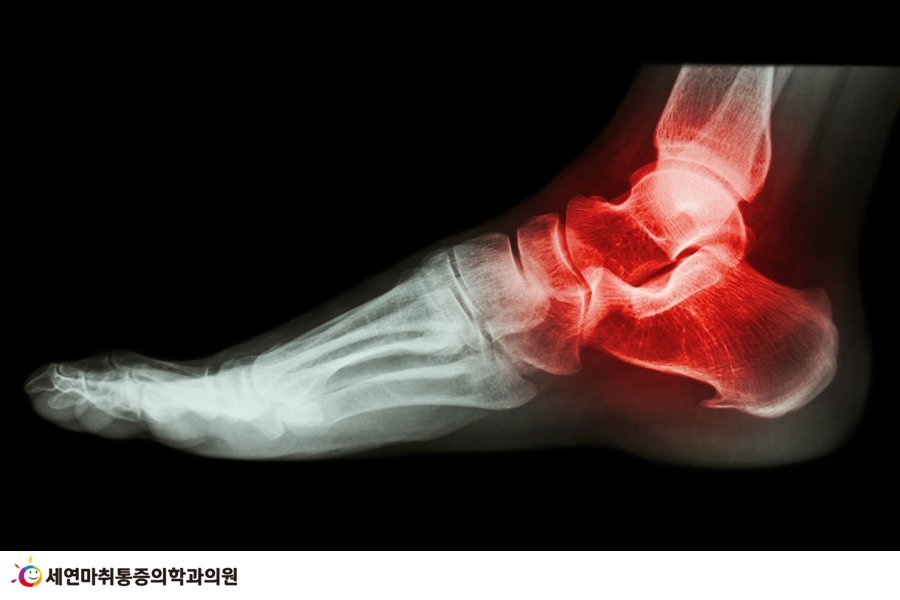

아차 하는 순간 발목 삐끗, 초기 대처의 중요성

요즘 들어 발목을 삐끗하는 ‘발목 염좌’로 저를 찾아오는 환자분도 덩달아 늘었습니다.

며칠 전에는 빙판길에 넘어져서 발목을 다친 환자도 있었고, 울퉁불퉁한 보도블록에 발이 걸려 넘어지면서 발목을 삐끗해 저를 찾아온 환자도 있었습니다.

발목염좌란? 발목의 심한 비틀림 혹은 발목이 접질리거나 낙상 및 교통사고 등 외부 충격으로 인해 주로 발생하며, 발목을 지지하는 인대들이 외부 자극에 의해 심하게 뒤틀리면서 염증을 유발하는 족부 질환입니다.

일상 속에서 발목을 삐끗하는 상황은 빈번하게 발생할 수 있지만, 이를 방치하면 예상치 못한 상황을 초래하게 됩니다.

사실 가벼운 발목 염좌는 며칠 휴식을 취하면 어느 정도 통증이 개선되지만, 발목을 삐끗한 순간 제대로 초기 대처를 하지 못하면 발목에 더 큰 무리가 가고 부상 정도가 심해질 수 있습니다.

추후 통증이 완화되었다고 해도 '다친 데 또 다치는 격'으로 반복적인 발목 염좌 증상(발목불안정증후군 혹은 만성인대불안정증)으로 발전할 수 있고, 자칫 만성 통증으로 이어질 수도 있습니다.

또, 인대가 많이 찢어지거나(보통 발목 염좌 2단계라고 합니다) 혹은 완전히 파열된 경우, 제대로 된 초기 대응(응급처치)과 적절한 치료가 이루어지지 않으면 인대와 뼈가 변형되는 등 2차, 3차적인 고통이 따를 수 있어 주의해야 합니다.